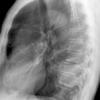

Case 2  Lingular pneum Lat

Date: 04/17/2005

Views: 7428